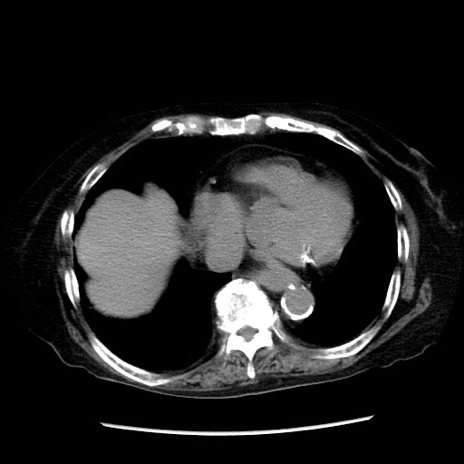

症例14(横断像)

冠状断像

【症例】 90歳代女性

【主訴】 腹痛・嘔吐

【現病歴】今朝から左側腹部痛を認めた。 経過観察していたが、嘔吐を認めたため来院。

【既往歴】 子宮癌術後

【身体所見】 意識清明、BP 127/54mmHg、P 98bpm Sp02 95%(RA)、BT 35.8°C、腹部平坦・軟腸ぜん動音聴取良好、右下腹部圧痛(+) 反跳痛なし

【データ】WBC 9800、CRP 0.46